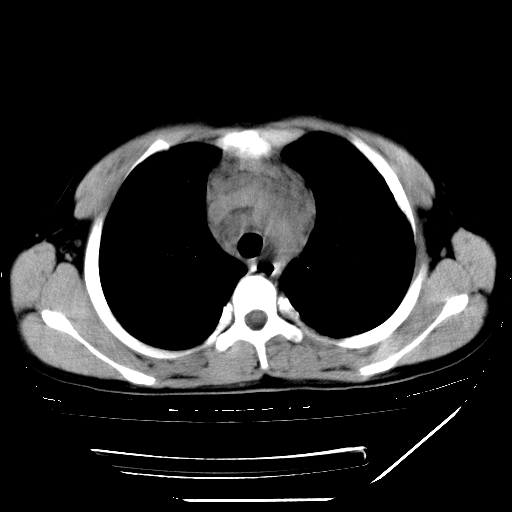

男,13岁,咳嗽、咳痰伴发热一周。

上纵隔课件多枚淋巴结,部分相互融合,左侧支气管壁增厚,肺纹理较右侧增粗,患者,男,13岁,

中上纵隔见多枚淋巴结肿大,部分相互融合成团片,左肺门增大,上叶支气管变窄,肺内多处斑片状 索条状及棉絮状致密影。临床“男,13岁,咳嗽、咳痰伴发热一周。”首先考虑:原发综合征!不除外淋巴瘤可能!

中上纵隔见多枚淋巴结肿大,部分相互融合成团片,左肺门增大,上叶支气管变窄,左肺支气管血管束增粗,可见磨玻璃样影。临床“男,13岁,咳嗽、咳痰伴发热一周。”首先考虑:淋巴瘤可能性大!

考虑:淋巴瘤可能性大。范围比较大,要是结核的话,症状应该比较明显且重些吧,次考虑原发综合征

淋巴瘤可能性大并肺部侵犯。